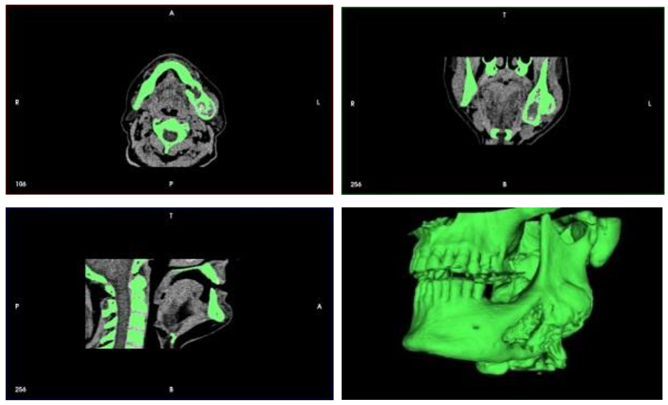

- phase 1: Conversion of the CT scan of the mandible from DICOM format to a 3D STL model

- phase 2: Model of the deformed part of the mandible before and after computer-assisted resection

- phase 3: Computer modeling of the implant